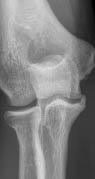

Radiography and computed tomography were performed (Figures 1–3). An aseptic necrosis was detected in the region of the tubercle of the coronary process in the fragmentation stage.

Fig. 1. Radiograph of the left elbow joint. Fragmentation stage of the region of the coronoid process tubercle